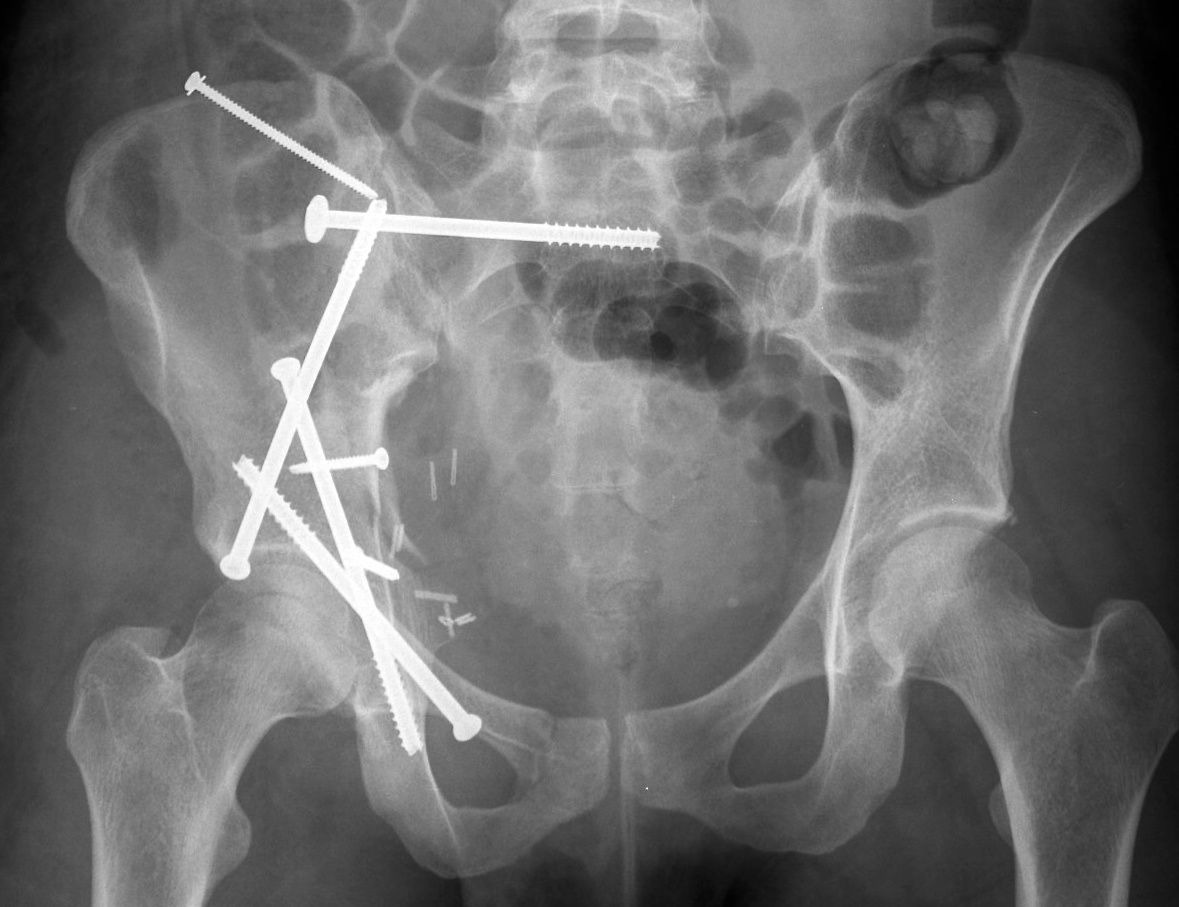

Нестабильный таз

Нестабильный таз 112 фотографий